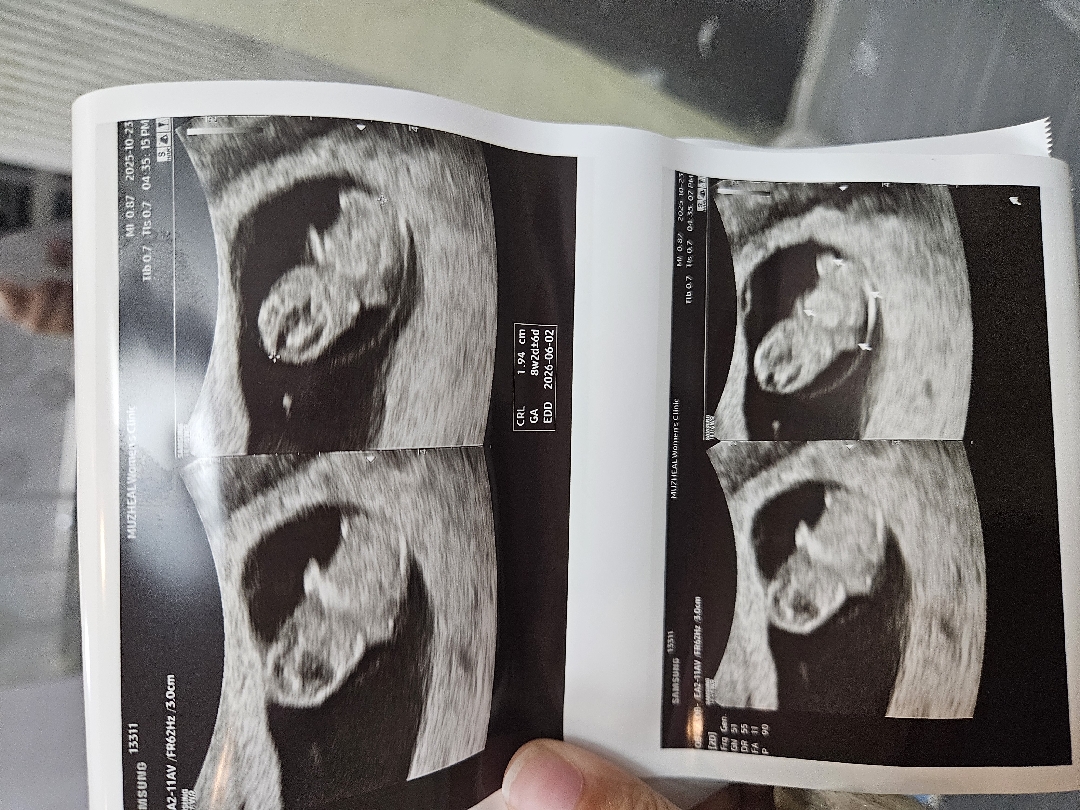

어제부터 약간 갈색냉+ 오늘 싸하게 아랫배 불편한 느낌이 있어서 택시타고 서브병원 하나 뚫어 진료보고왔어요..!! 그결과 이렇게 귀엽고 하찮은 2등신의 젤리곰...ㅠㅠ서브병원이 출산까지 하는 병원이 아니다보니 의사선생님께서도 애기를 어머머 하면서 너무 귀여워하며 초음파 봐주셔서 이미 걱정은 저멀리 너무 기분좋게 귀여운 모습 실컷보고 왔습니당 ㅋㅋㅋ 오늘이 8주차 그리고 다음주 원래 정기검진이라 9주차 젤리곰 한번 더 볼수 있겠어요😊🥰